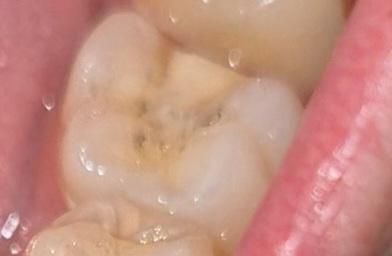

하악 제1 대구치에 있던 금 인레이가 치실을 하다가 빠져서 크라운을 권유받았습니다. 그런데 대합치인 상악 제1 대구치가 금인레이를 해서 그런지 크랙이 좀 있습니다. 지르코니아 점점 치아 강도와 비슷해져 간다는 소리를 듣긴 했습니다만. 이런 경우에는 지르코니아보단 금이 더 나은 선택일까요? 사진은 순서대로 상악, 하악 제1 대구치입니다.

• 1번 째 사진

• 2번 째 사진